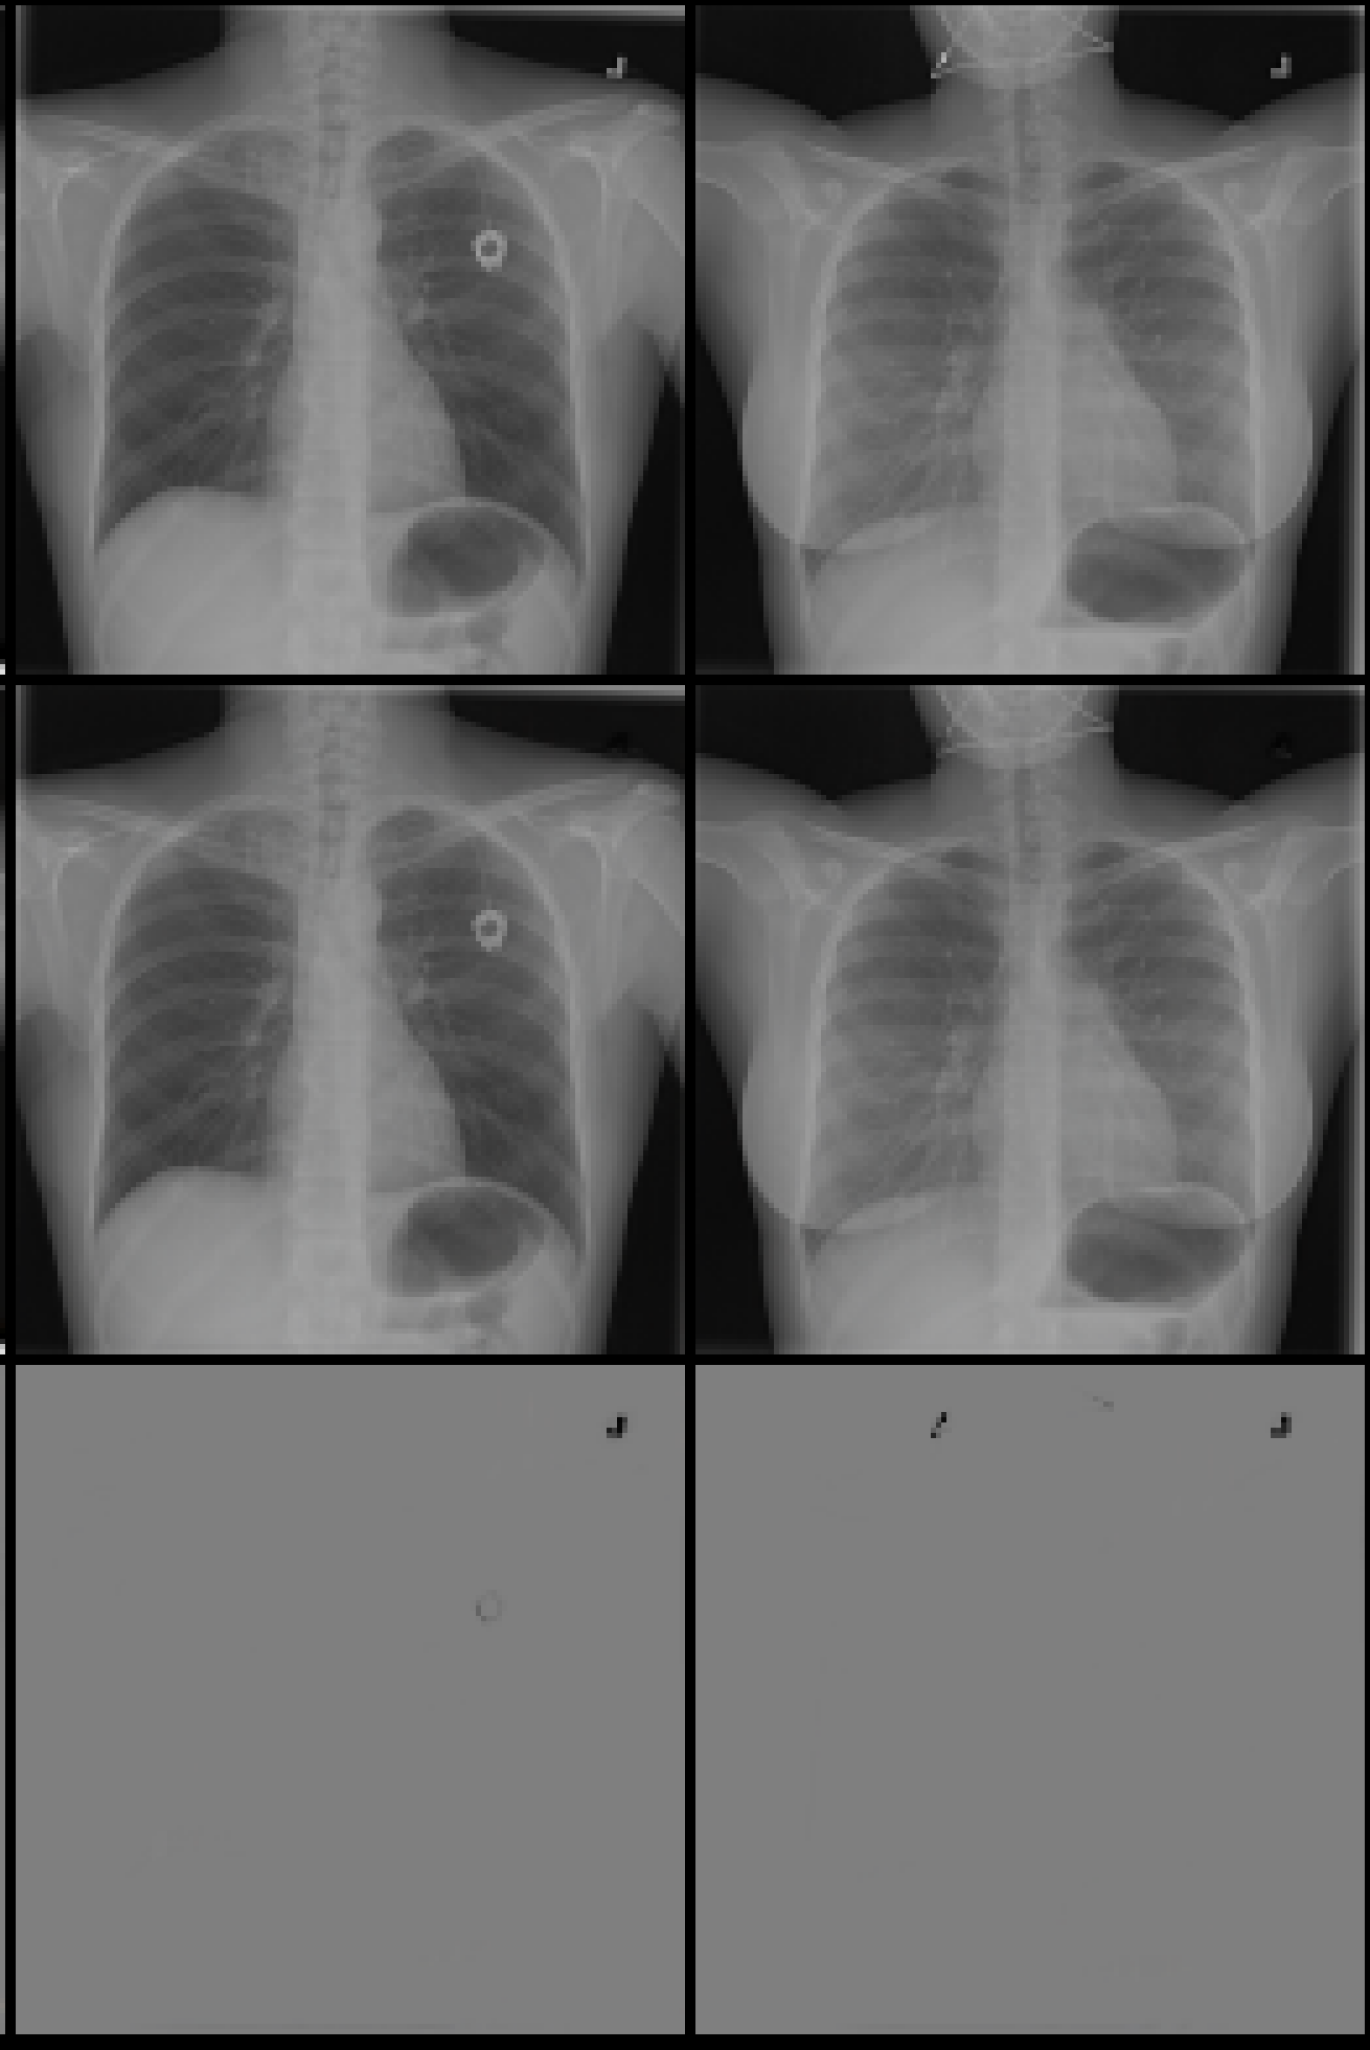

Original Lense output Difference

Refer to caption

(a) Normal

(b) COVID

Figure 5: Lens output and attention on x-ray images from the covid-qu-Ex dataset for the classes classes COVID and Normal. Row 1 shows original images. Row 2 shows the output of the lens. Row 3 shows the difference between rows 1 and 2.